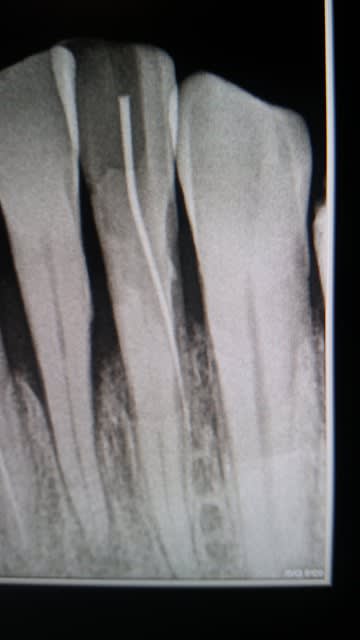

Voila un cas d'endo sur incisive inf.

J'ai pas mal galère pour trouver l'entrée canalaire (canal calcifié), puis finalement j'y suis, quel bonheur!

Sauf qu’après une petite radio de contrôle je suis bien rentré mais pas ou il faut, une belle fausse route.

Je vous ai mis une radio pour vous faire une idée.